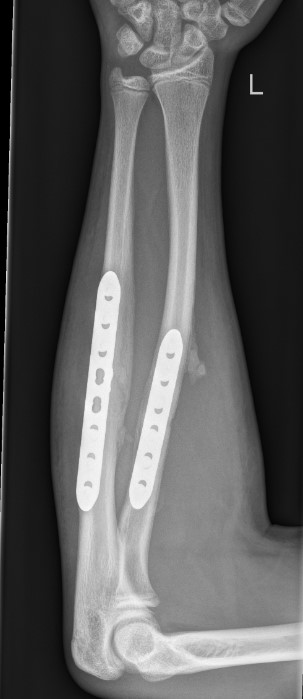

ORIF with plates

AO surgery Henry approach to radius

AO surgery compression plating technique

Single versus Double plate

- RCT of 100 patients with both bone forearm fractures

- ulna plating versus ulna & radius plating

- no difference in outcome, range of motion or union rates

- some loss of position in radius when not plated